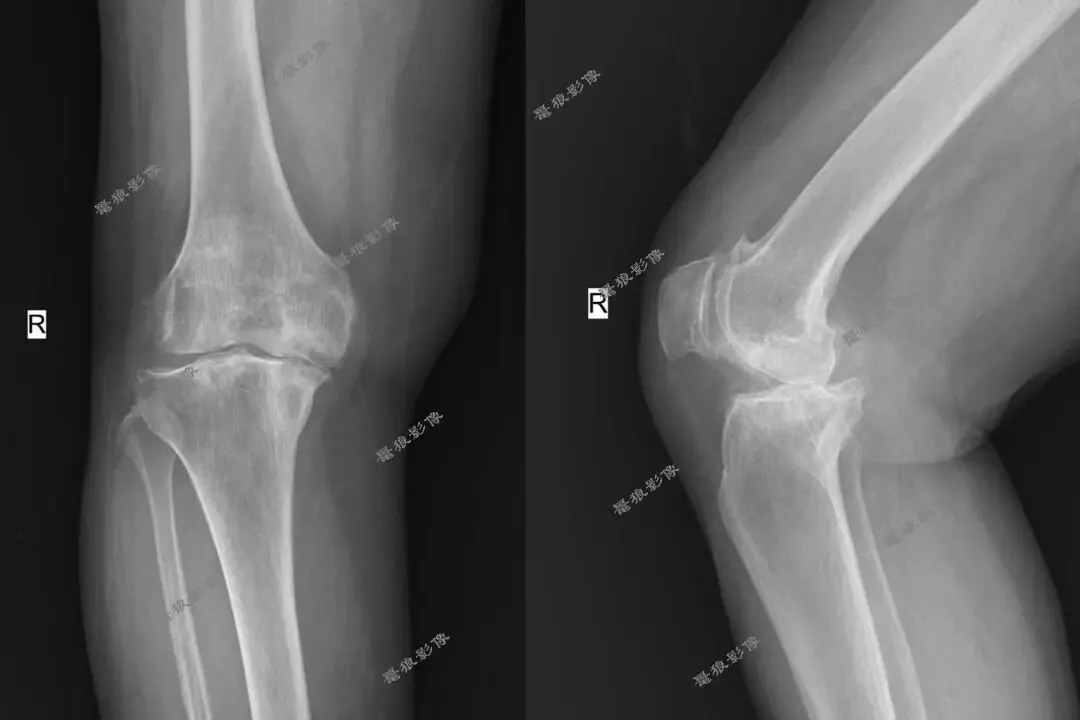

F,70y,外伤致右膝部疼痛。

半年前右膝关节退行性骨关节病,行右膝关节置换术后。

术前: